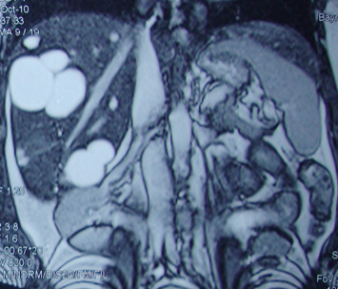

Şəkil. Hepatoblastoma

Diaqnostikası

Şübhə

• Uşaq yaşlarında qaraciyərdə törəmə tapılarsa ilk növbədə hepatoblastomadan şübhələnmək lazımdır.

• Alfa-fetoprotein əksər hallarda yüksəlir.

Dəqiqləşdirmə

• Görüntüləmə əlamətlərinə görə qaraciyərin digər şişlərindən ciddi fərqlənmir- hipoexoik, hipodens, hipervaskulyar, T1-də hipointens, T2-də hiperintens, heterogen.

• Dəqiq diaqnozu patohistoloji müayinədə qoyulur.